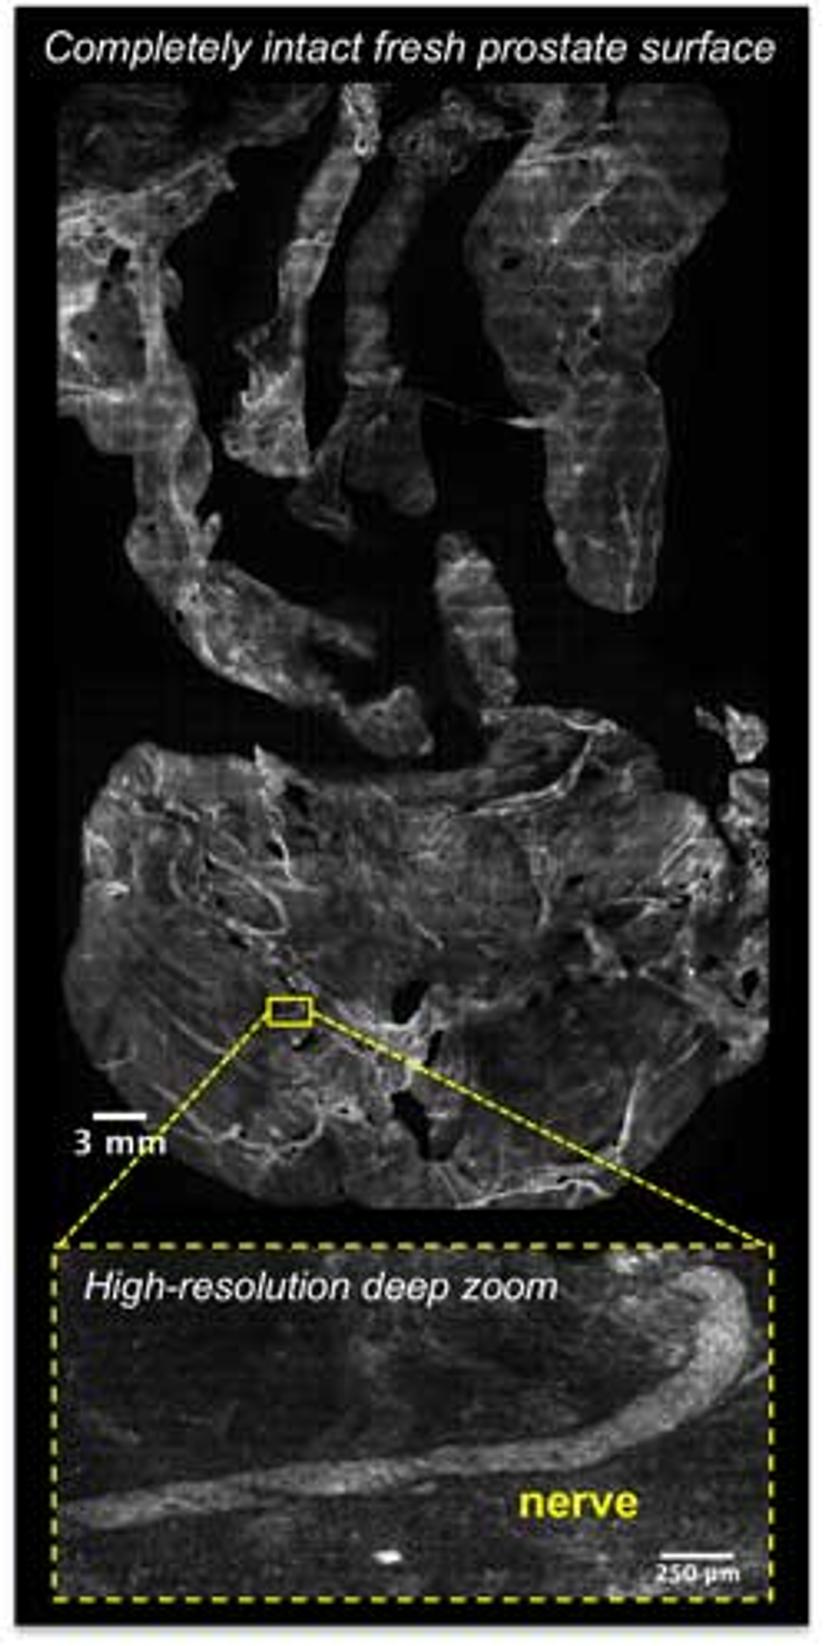

In a study published in Scientific Reports, the team used structured illumination microscopy (SIM) to directly examine the surface of the prostate taken out during surgery. “As opposed to a single layer of cells in vitro or a sliced piece of frozen tissue section, we’re looking at tissue that’s thick and fresh out of the body, basically the whole organ. We need to cut it somehow. Rather than physically cut them, we optically cut it,” explains Dr. Brown.

A large Google Maps-style image of the entire surface of a freshly removed tumor can be searched for remnants of tumor at the edge, providing feedback to surgeons. (Image courtesy of the Brown lab)

Dr. Brown describes how he works in collaboration with surgeons and clinical pathologists: “During surgery, the surgeon can leave much of the normal tissue adjacent to the prostate to maximize postoperative function. They then give us the resected organ. We dip the organ in dyes, put it on a flatbed scanner, and take very large Google Maps-style images of the whole surface. Then the pathologist, who is sitting in their office, gets the images online. They take a look and decide, ‘Do I see any cancer on the edge of this specimen?’ If they do, they call the operating room and tell the surgeon, ‘Here is where I see residual tumor. You need to go back and cut more tissue.’”